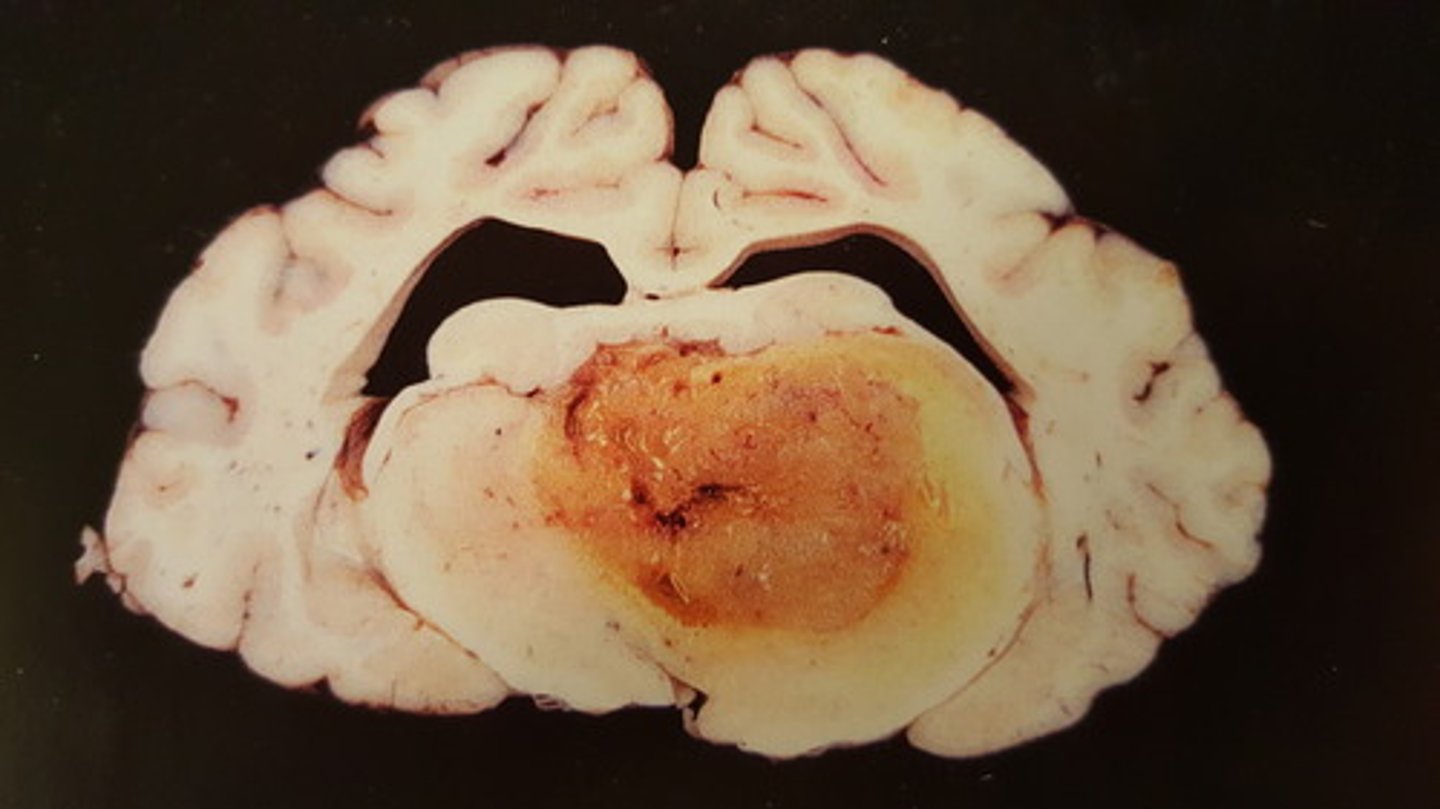

oligodendrogliom, benign neoplasi

Hjerne fra okse. Patoanatomisk diagnose?

astrocytom, benign neoplasi

Hjerne fra okse. Patoanatomisk diagnose?